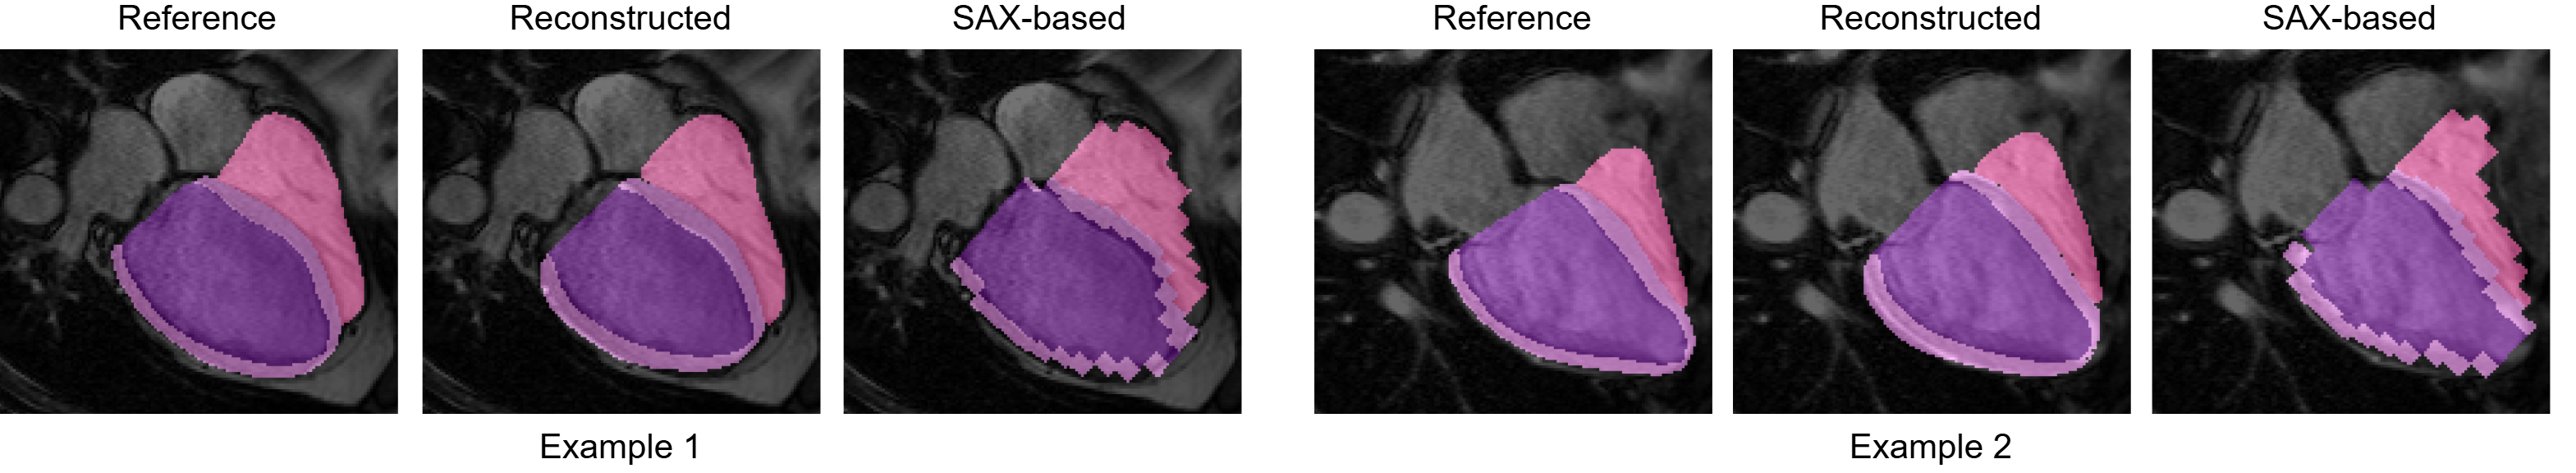

As shown, all the metrics computed for the proposed method in reconstructing 4CH LV and RV segmentations notably outperform those directly extracted from low-resolution SAX. Figure 3 shows two examples of reference, reconstructed and SAX-based 4CH segmentations of LVBP, MYO and RV. These show that the model compensates for CMRI’s anisotropy and inter-slice misalignment, leading to smooth complete shapes.

Refer to caption

Figure 3: Examples illustrating a 4CH CMRI overlaid with reference, reconstructed and SAX-based segmentations of LVBP (darker purple), MYO (lighter purple) and RV (pink).